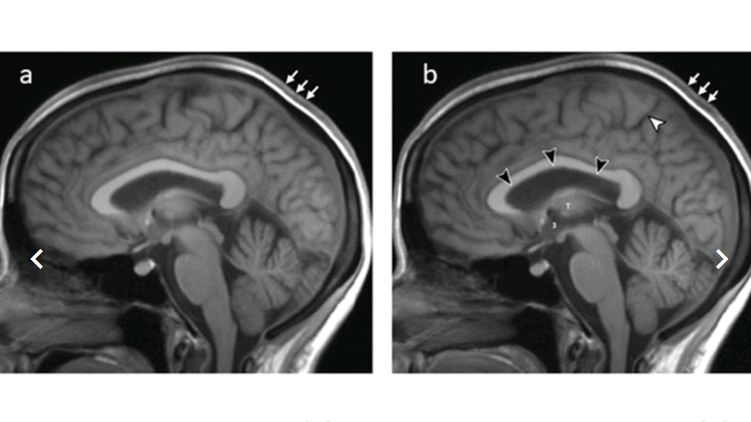

Всем 11 участникам исследования провели МРТ-сканирование мозга до начала полета, на следующий день после возвращения, а также через месяц, три месяца, полгода и год.

После полета у астронавтов наблюдалось увеличение объема головного мозга и циркулирующей в нем жидкости в среднем на 33 миллилитра (это 2%). Изменения сохранились и через год после окончания полета: объемы были увеличены на 28 миллилитров. Кроме того, у шести астронавтов наблюдалась небольшая деформация гипофиза - ключевого для эндокринной системы участка мозга. Его размер в среднем уменьшился с 5,9 до 5,3 миллиметров у 6 из 11 астронавтов.

Увеличение объемов головного мозга и циркулирующей в нем спинномозговой жидкости вызвано повышением внутричерепного давления из-за длительного пребывания в условиях микрогравитации.

Одно из наиболее распространенных последствий повышения давления - отек зрительного нерва и нарушения зрения. Изменения давления также способно привести к нарушениям когнитивных функций.

Ученые пришли к выводу, что изменения мозга вследствие длительного пребывания в космосе постоянные. По крайней мере, они сохраняются в течение года, а динамики в сторону возвращения к норме нет.